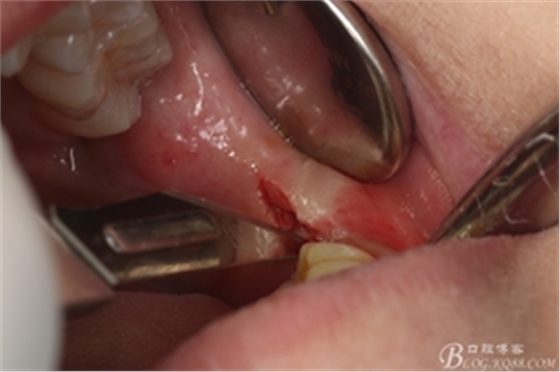

圖8. 翻瓣:建議翻小瓣

圖9.翻開(kāi)瓣,可見(jiàn)38部分牙冠暴露